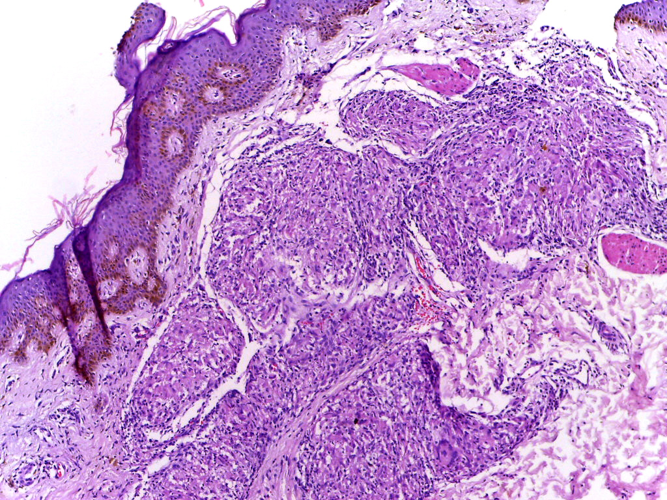

Section of skin showing epithelioid granulomas in the dermis and reduction in the number of appendages. (Department of Pathology, Calicut Medical College via Wikimedia Commons)